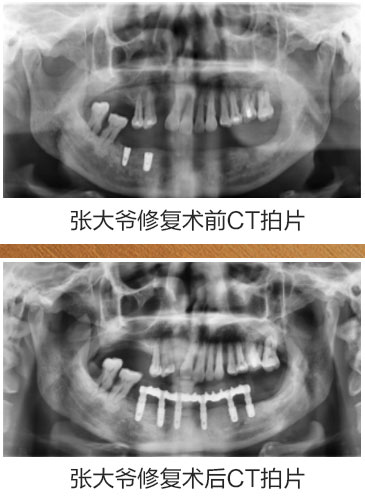

患者:张大爷 年龄:60多岁

自诉情况:在其他医院种牙失败,种六颗,现在掉了四颗,在种牙上花了很多冤枉钱和时间,精疲力尽,受罪不说还赔上了健康。

诊断治疗:对患者全身状态评估,检查口内状况及影像数据,给出多种修复方案,患者知情同意,选择数字化导板种植,埋入愈合,3个月后二期修复,咬合重建,金塑桥过度,钛支架和烤瓷牙固定种植义齿修复方案,帮助患者恢复口腔功能及身体健康。

修复主治医生:德伦口腔东风总院种植科罗朝阳副主任